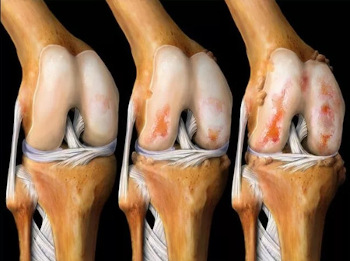

NU UITAȚI: ARTRITA ȘI artroza DISTRUG ȚESUTUL CARTILAGINOS ÎN 3 ANI! Din păcate, nu există un ajutor pentru artrită, doar intervenția chirurgicală poate ajuta...

Efectele artrozei asupra cartilajului articulației genunchiului.

Din păcate, specialistul avea dreptate... După 2 luni era insuportabil de dureros să stau în picioare, remediile și analgezicele nu mai funcționau, deși cheltuisem o mulțime de bani pe ele, iar remediile îmi afectau grav stomacul și ficatul - am fost nevoită să renunț la ele! A trebuit să-mi cumpăr un scaun cu rotile și să-l folosesc pentru a mă deplasa prin casă... Specialistul meu a spus că artroza distruge cartilajul în 3 ani, dar părea să înceapă mult mai repede, cel mai interesant lucru este că nu simțeam durerea articulară, iar apoi, dintr-o dată, s-au agravat și, brusc, am ajuns într-un scaun cu rotile, fără nicio speranță de vindecare, îmi amintesc doar lacrimile care îmi veneau în ochi, a fost cea mai grea perioadă din viața mea......